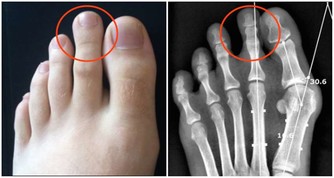

4下肢水腫

腎病患者也會下肢水腫,但肝癌患者的水腫,一般發生在腳踝和下肢,甚至能直接滲出水液。這是因為肝臟癌變腫大,壓迫腿部靜脈導致的。